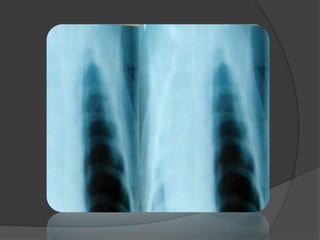

IMAGERIE:

LA RADIOGRAPHIE DU THORAX

 Opacité généralement lobaire inférieure,

+++ G, bien limitée homogène pouvant être

le siège d’un niveau hydro-aérique

 Arrondie → SIL / Triangulaire → SEL

 Artère systémique:

rarement visualisée.

image basithoracique interne tubulée,

homolatérale.